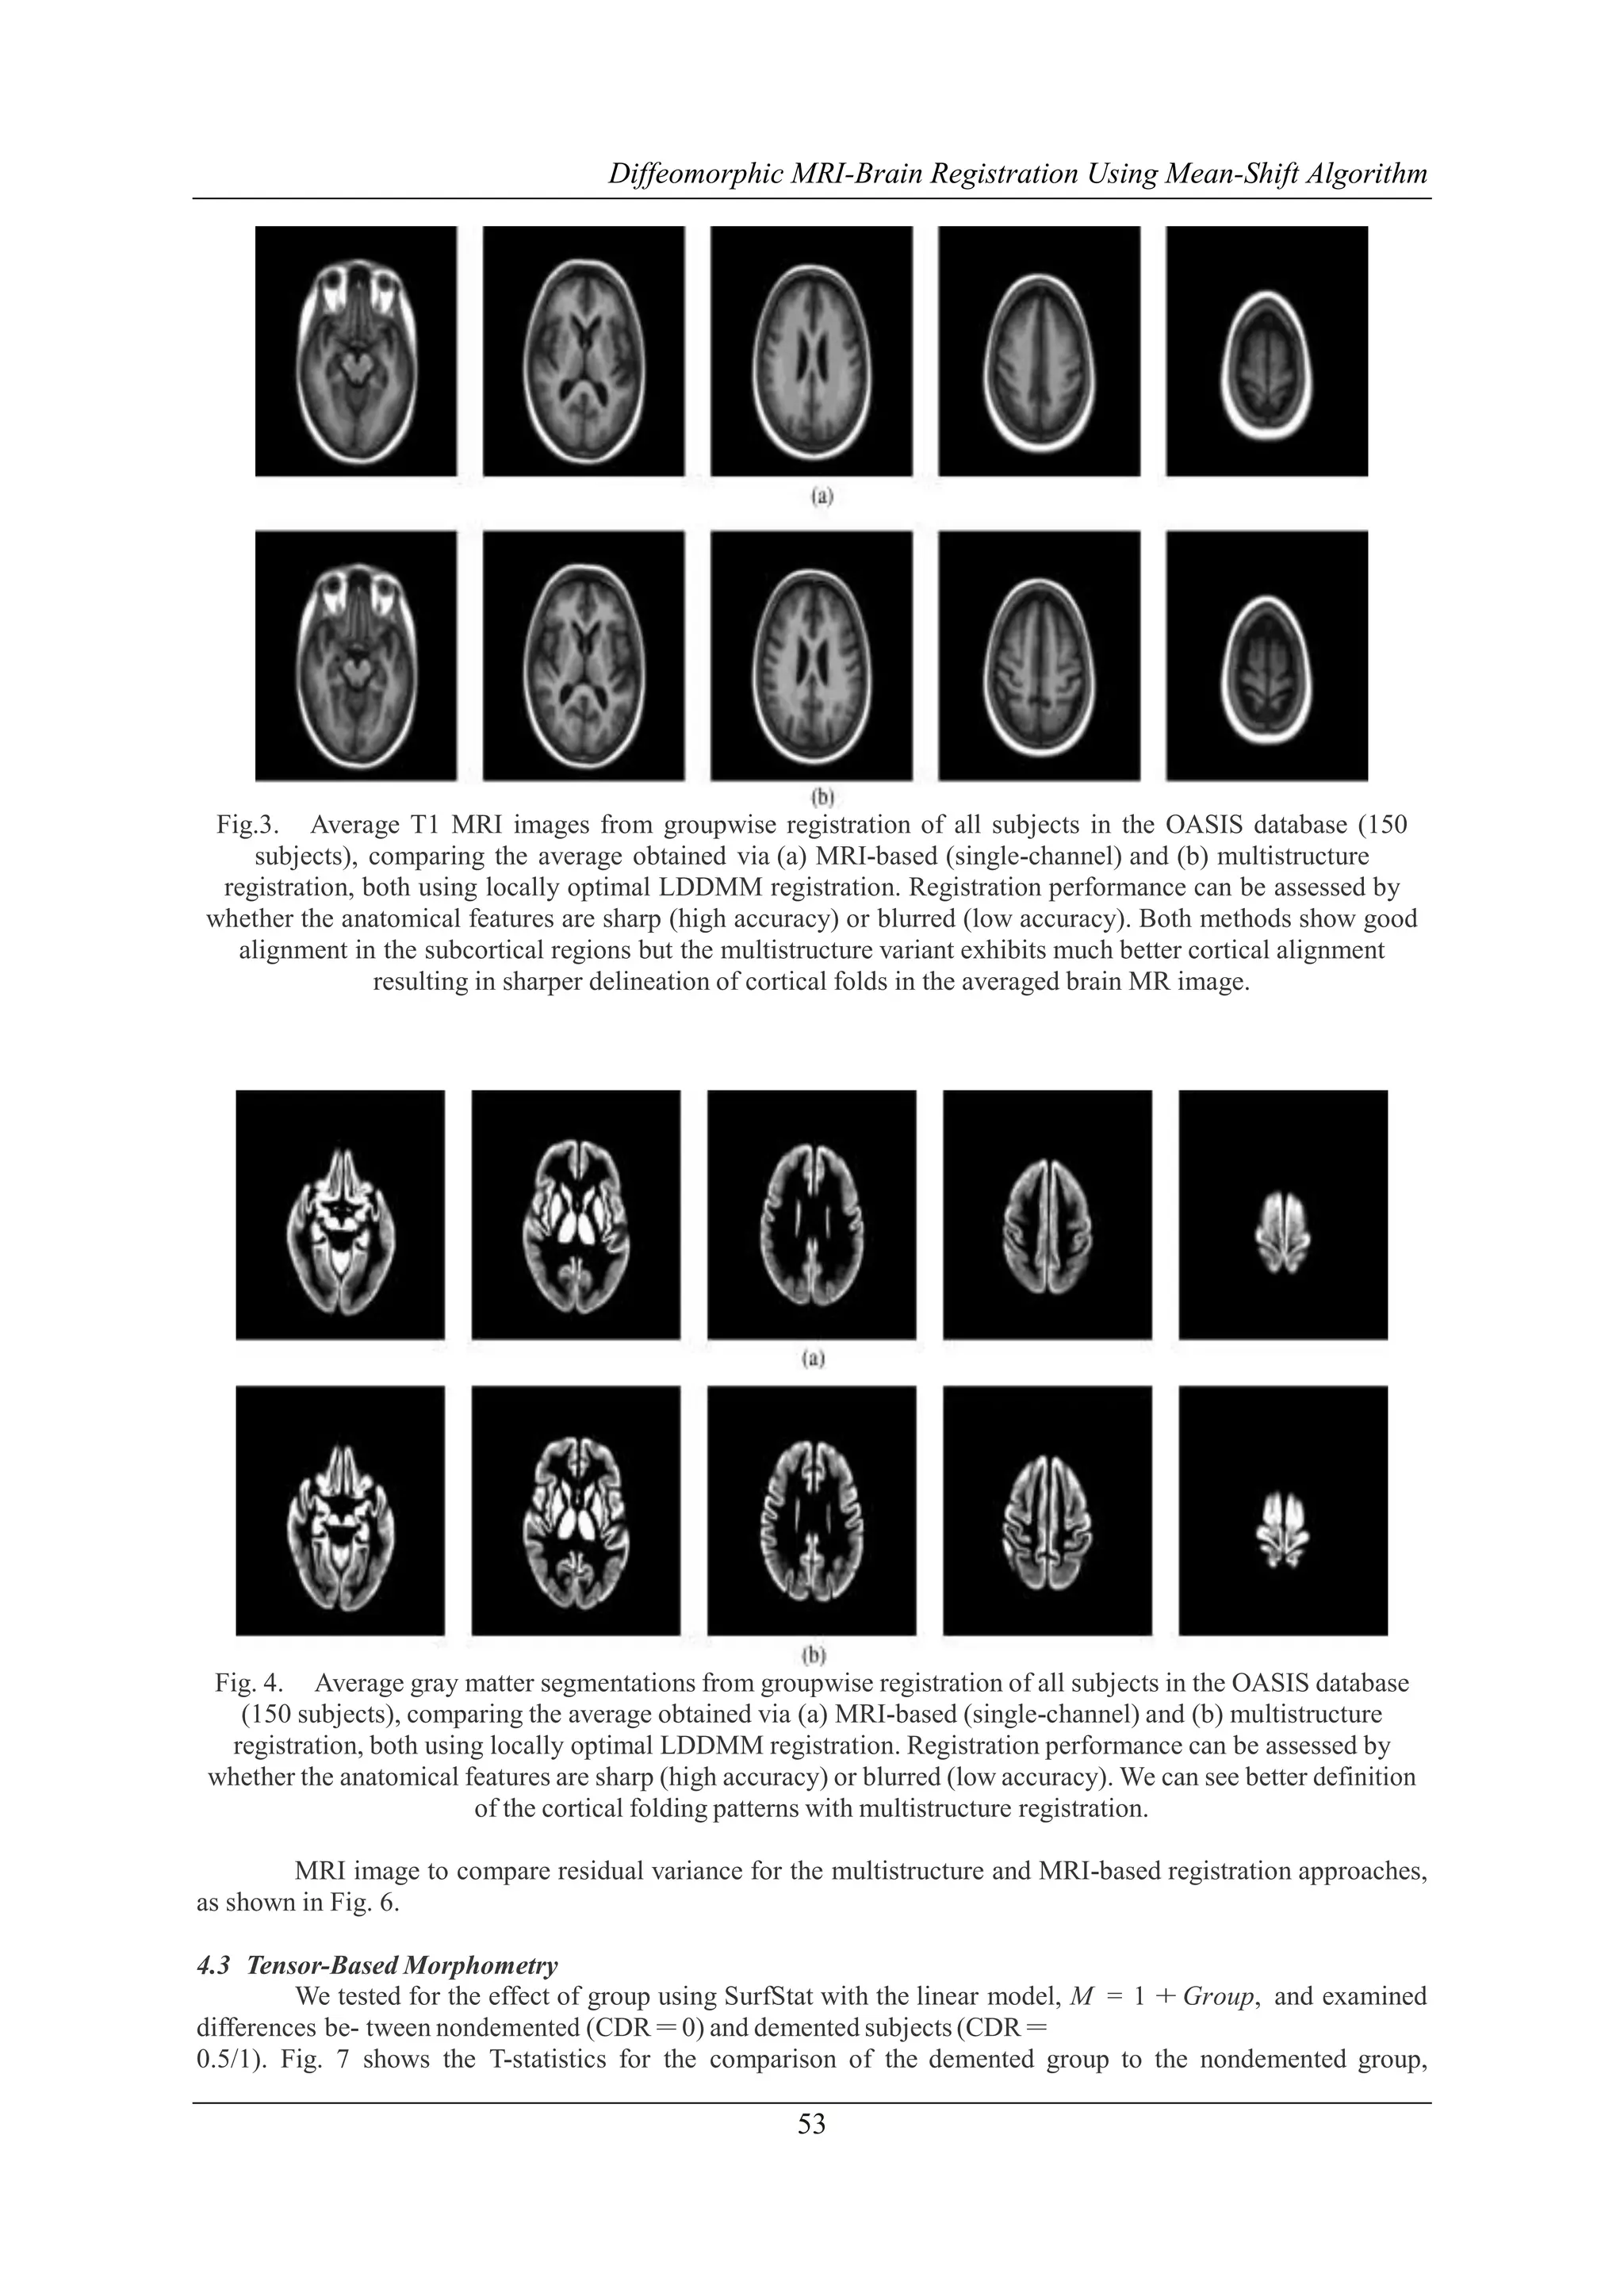

4.2 Groupwise Average Atlas

To qualitatively evaluate the performance of our multistruc- ture and MRI-based groupwise average

atlas generation, we performed them on the OASIS 150 subject set, generating an LDDMM MultiStruct average

and an LDDMM MRI average. Fig. 3 shows representative axial slices of the average T1 MRI image, generated

by transforming each subject’s T1 MRI im- age to the average space, using the final mappings from the groupwise average, and performing voxel-wise averaging. In regions where the anatomy is not well aligned and thus

has a mixture of different tissue types from the subjects, the image is effectively blurred. In contrast, where the

anatomy is well aligned the anatomical boundaries are effectively sharper. We see here that the multistructure

approach improves registration in many regions, especially cortical regions, as can be seen by the sharp and

well-defined boundaries. To further investigate this effect, we transformed the gray matter segmentations from

each subject to the average space to generate an average gray matter mask, as shown in Fig. 4. We see a similar

pattern here,

with greater definition of cortical folding patterns in the average generated by multistructure registration.

Fig.3. Average T1 MRI images from groupwise registration of all subjects in the OASIS database (150

subjects), comparing the average obtained via (a) MRI-based (single-channel) and (b) multistructure

registration, both using locally optimal LDDMM registration. Registration performance can be assessed by

whether the anatomical features are sharp (high accuracy) or blurred (low accuracy). Both methods show good

alignment in the subcortical regions but the multistructure variant exhibits much better cortical alignment

resulting in sharper delineation of cortical folds in the averaged brain MR image.

Fig. 4. Average gray matter segmentations from groupwise registration of all subjects in the OASIS database

(150 subjects), comparing the average obtained via (a) MRI-based (single-channel) and (b) multistructure

whether the anatomical features are sharp (high accuracy) or blurred (low accuracy). We can see better definition

of the cortical folding patterns with multistructure registration.